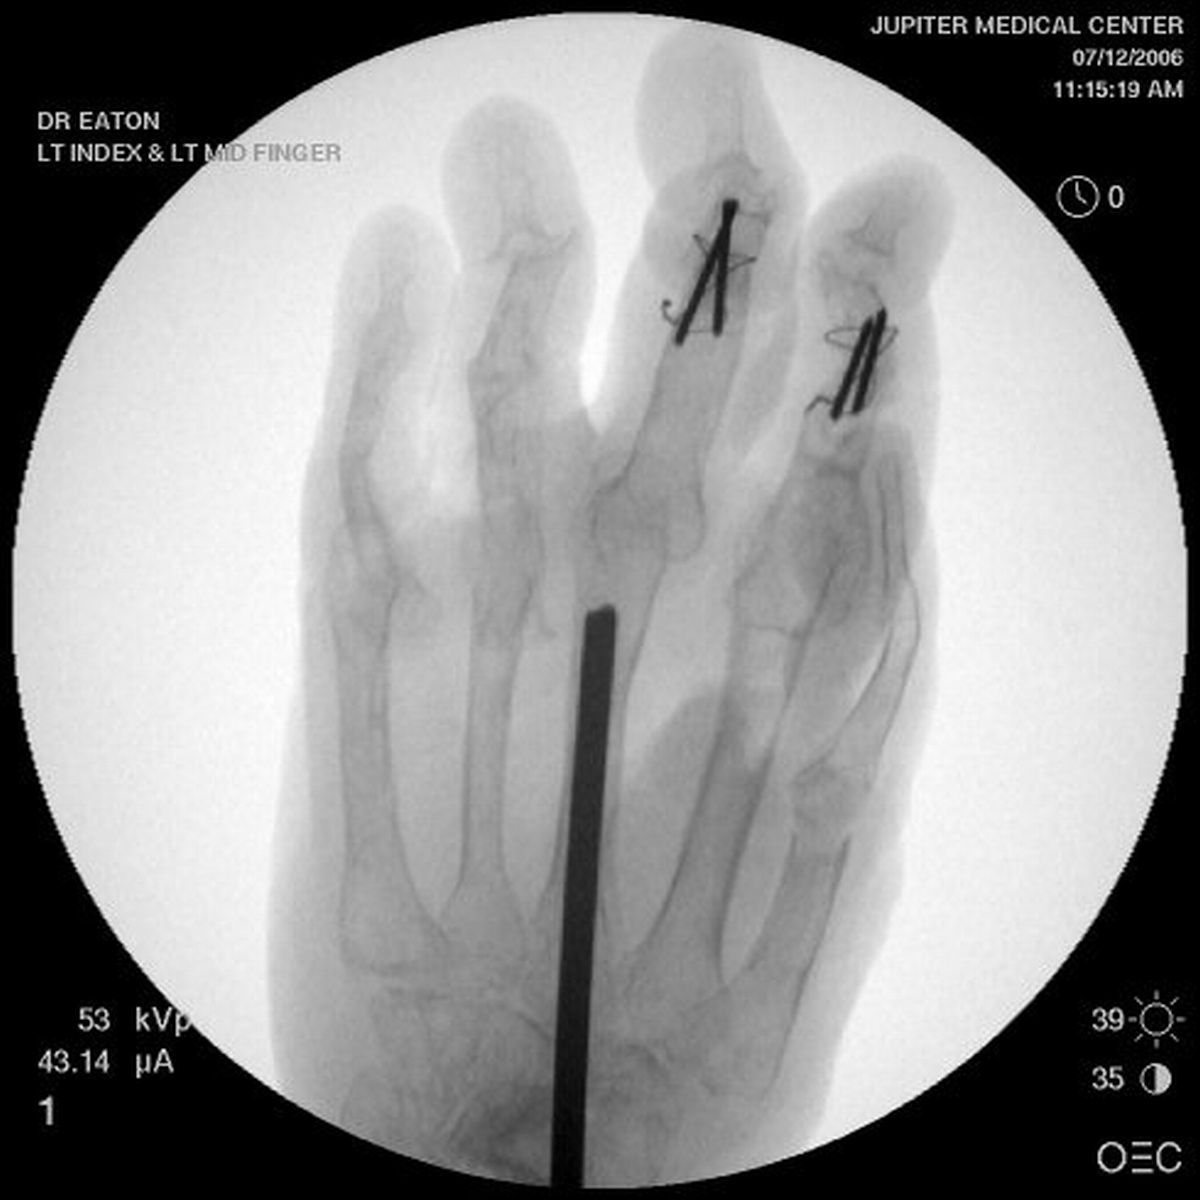

Her greatest desire was pinch reconstruction. This was approached in two stages: wrist fusion, implant removal and fusion of the index and middle PIP joints, followed by index and middle MCP arthroplasties. There are several alternative approaches, including index MCP fusion and revision PIP arthroplasties.

Below are xrays after the first set of reconstructions.